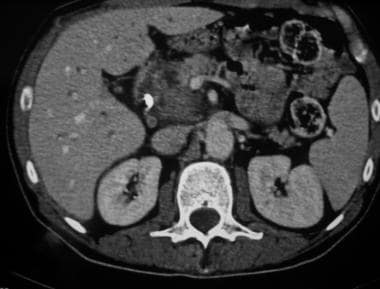

1. Imaging of Pancreatic Masses by Dr. Zainab Vora

In this super informative lecture, Dr. Zainab Vora discusses the core of imaging pancreatic masses in detail.

Key Highlights:

• Adenocarcinomas: The most common pancreatic mass in clinical practice.

• Cystic and Neuroendocrine Tumors: High-yield topics for exam

• Surgical Implications: Anatomy and Surgical decision-making in pancreas surgeries: Whipple’s procedure, distal pancreatectomy

• Cross-sectional Anatomy and Mastering the art of CT and Ultrasound imaging.